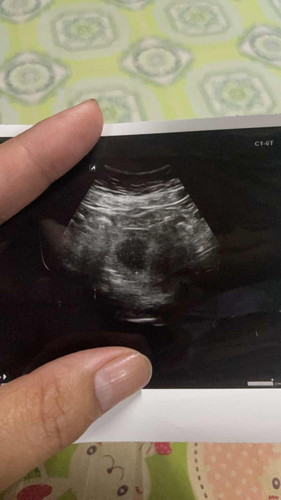

8 สัปดาห์ยังไม่เจอน้องเลย เป็นคนหน้าท้องหนาด้วย อ้วนหนัก 95 ค่ะ ซาวด์แค่ทางหน้าท้องค่ะ ไม่ได้ซาวด์ทางช่องคลอด มีโอกาสจะเจอน้องมั้ยคะ

ลองซาวด์ผ่านช่องคลอดค่ะ อาจเจอตัวน้อง บ้านนี้ก็หนักเท่ากัน ผ่านหน้าท้องไม่เจอ

8แล้วน่าจะเจอนะคะ บ้านนี้แม่หนัก85ค่ะ ซาวหน้าท้องตอน8+3